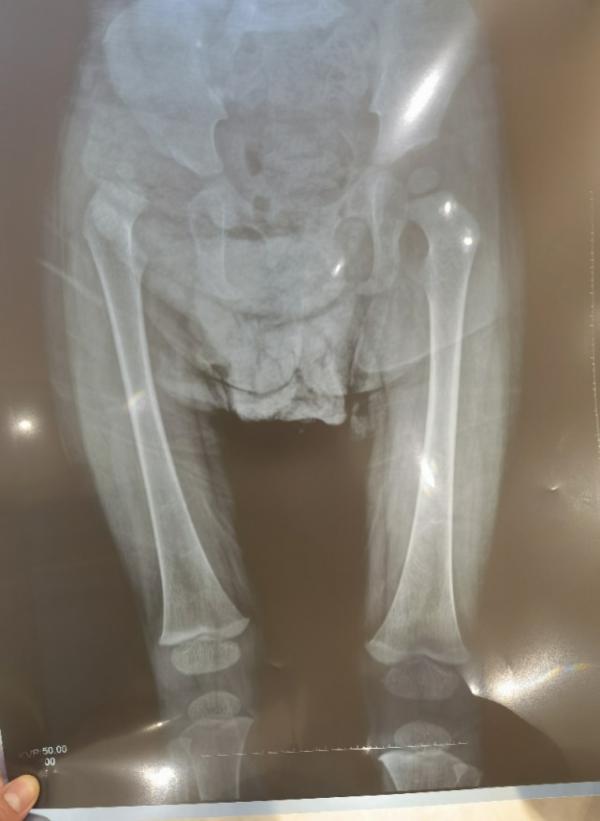

X线片显示患儿左侧先天性髋关节发育不良,股骨头脱位

“她的左腿比右腿短1-2厘米,对于一个身高只有60多厘米的小孩子来说,这种差距是非常明显的,这也是她跛行的原因。”李玉希医生表示,正常的股骨头应该位于关节窝里,髋关节脱位使小腿骨及大腿骨向上移动,从而导致整个腿骨发育不正常。